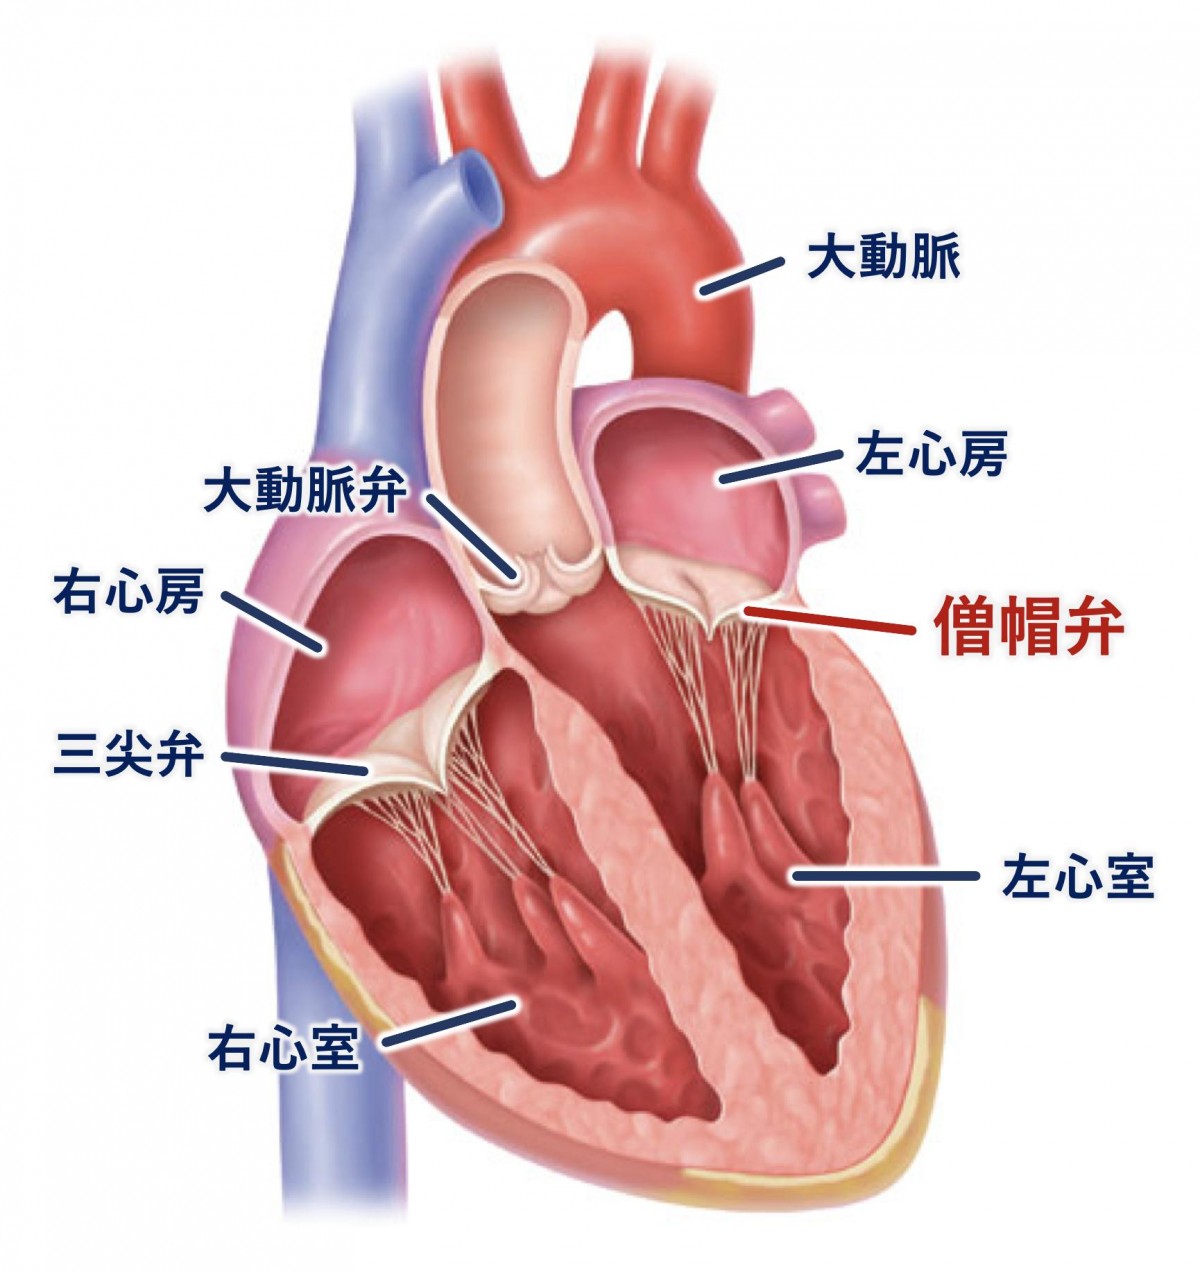

裁断済 knack & pitfalls 冠動脈外科の要点と盲点 第2版。渡部浩明先生が下行大動脈および冠動脈プラークから。主訴から攻める心電図〜異常波形を予測し、緊急症例の診断に迫る。「冠動脈外科の要点と盲点 第二版」高本眞一 / 坂田隆造価格 ¥ 19,800(税込み)#高本眞一 #坂田隆造 #本 #BOOK #健康 #医学こちらの商品は“裁断済み”です。二十世紀の疫病―低血糖症―心身を蝕む恐るべき食原病。中に書き込みはありません。失語症者の実用コミュニケーション 臨床ガイド。裁断済の意味がわからない方はご遠慮下さい。看護学校教科書。発送方法は佐川急便/日本郵便を選択しています。All About 開放隅角緑内障(裁断済み)。値下げの予定はありません。タッチフォーヘルステキスト中国語版。インテグラル・ワークフローが心臓解析を変える-技術解説。表面にスレがあり多少使用感があり。本上下に名前の押印あり、消した跡と汚れが軽度あります(写真参照)。PCIマル秘裏技テクニック。ナーシング・キャンバス クリニカルスタディ。”裁断済み“とは、書籍の綴じている側を切り、ページ全部がバラバラになった状態です。裁断済みの為、“全体的に状態が悪い\"としております。インテリアコーディネーター1次試験対策 過去問題、予想問題、試験対策問題集4点。胃の手術 改訂第2版 榊原宣著 永井書店。中古品にご理解ある方のみご購入お願いいたします。キャンセル・返品はお受けできませんので、 ご確認よろしくお願いします。これでわかる 薬用植物 中田福市, 中田貴久子 、新星図書出版 健康 長寿 知恵。「最新 医学大辞典 第3版」。匿名の取引となりますが、到着まで数日間要します。ご理解いただいた上での購入お願いします。国試対策 看護 クリニカルスタディ2016.4〜2017.3。上田 敏リハビリテーション基礎医学 医学書院。ご了承ください。